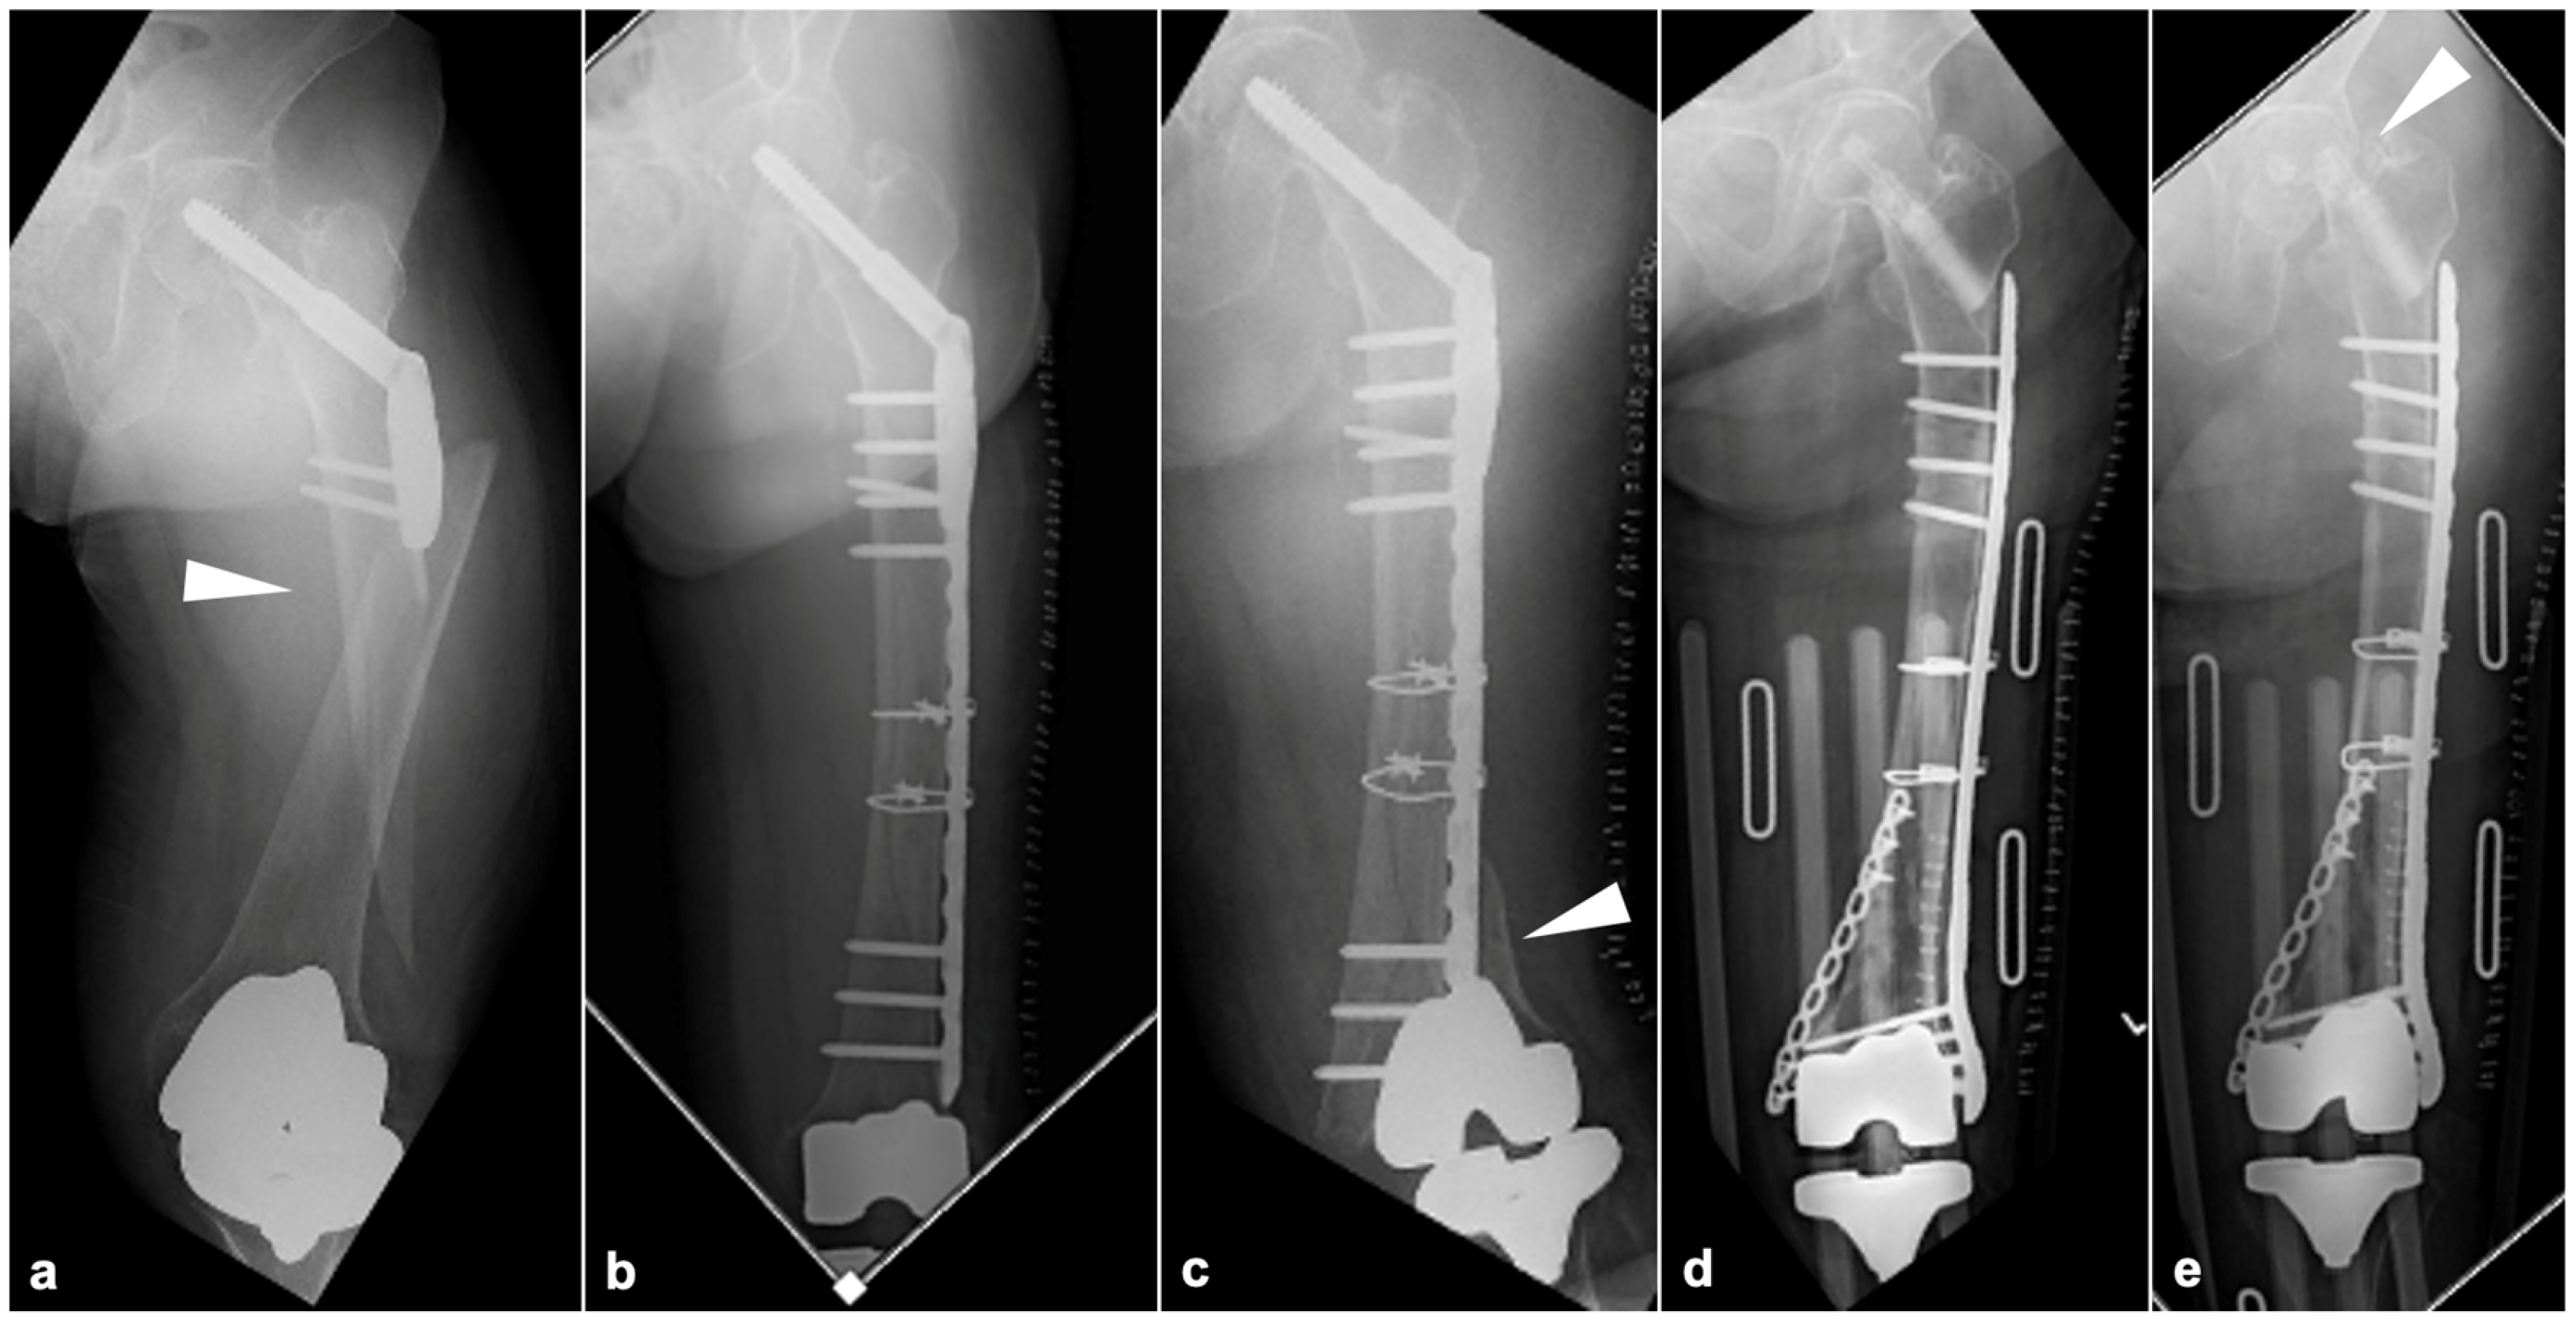

2.3.1. BHA/THA

2.3.2. SFN

2.3.3. TKA